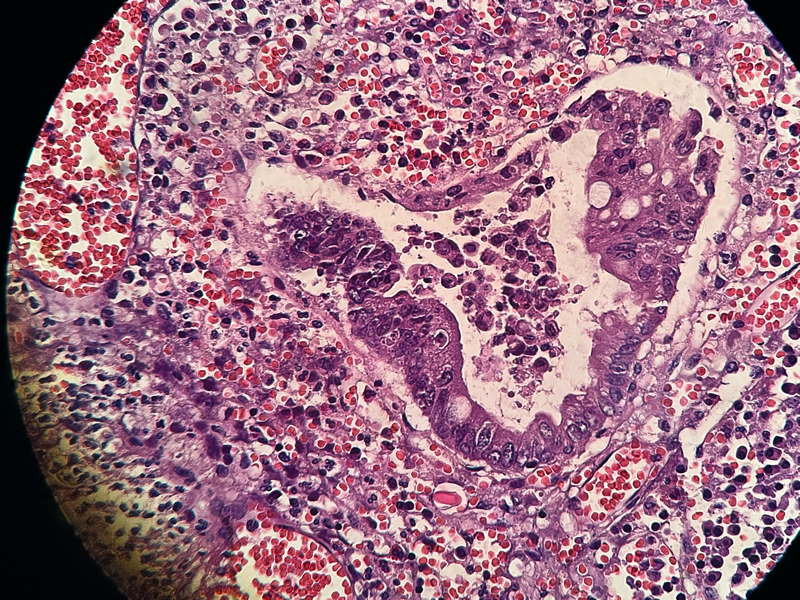

性别

女

年龄

54

临床诊断

急性阑尾炎

一般病史

持续性右下腹痛8小时

标本名称

阑尾

大体所见

阑尾约7.1cm ,直径约1.0-1.2,局部有脓苔

请各位老师看下这有没有问题,担心漏诊

化脓性阑尾炎。